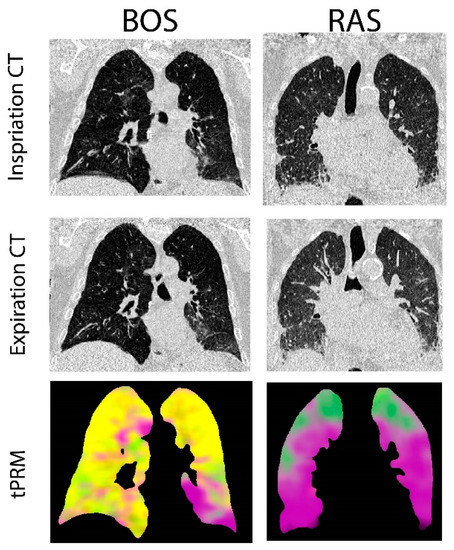

3.2. Representative Cases

Provided in Figure 1 are CT coronal views of the thoracic region with lungs at full inspiration and expiration for a patient with BOS and one with RAS. The BOS case is a male diagnosed with BOS 206 days post-transplant. This patient had a FEV1pp of 17% and FEV1/FVC of 0.4 when undergoing second transplantation. The RAS case is a female diagnosed with RAS 2649 days post-transplant. This patient had a FEV1pp of 50% and FEV1/FVC of 0.88 when undergoing second transplantation. The corresponding volume density maps for PRM-derived normal parenchyma (green), fSAD (yellow) and PD (magenta) are also presented. The lung transplant recipient who developed BOS had more PRM-derived fSAD distributed throughout the lungs, whereas the patient who developed RAS had more PRM-derived PD (Figure 1).

Figure 1. Representative cases diagnosed with BOS and RAS. Presented are the coronal view of CT scans acquired at inspiration and expiration with corresponding topological parametric response mapping (tPRM)-derived volume density maps for normal parenchyma (green), functional small airways disease (fSAD; yellow) and parenchymal disease (PD; magenta).